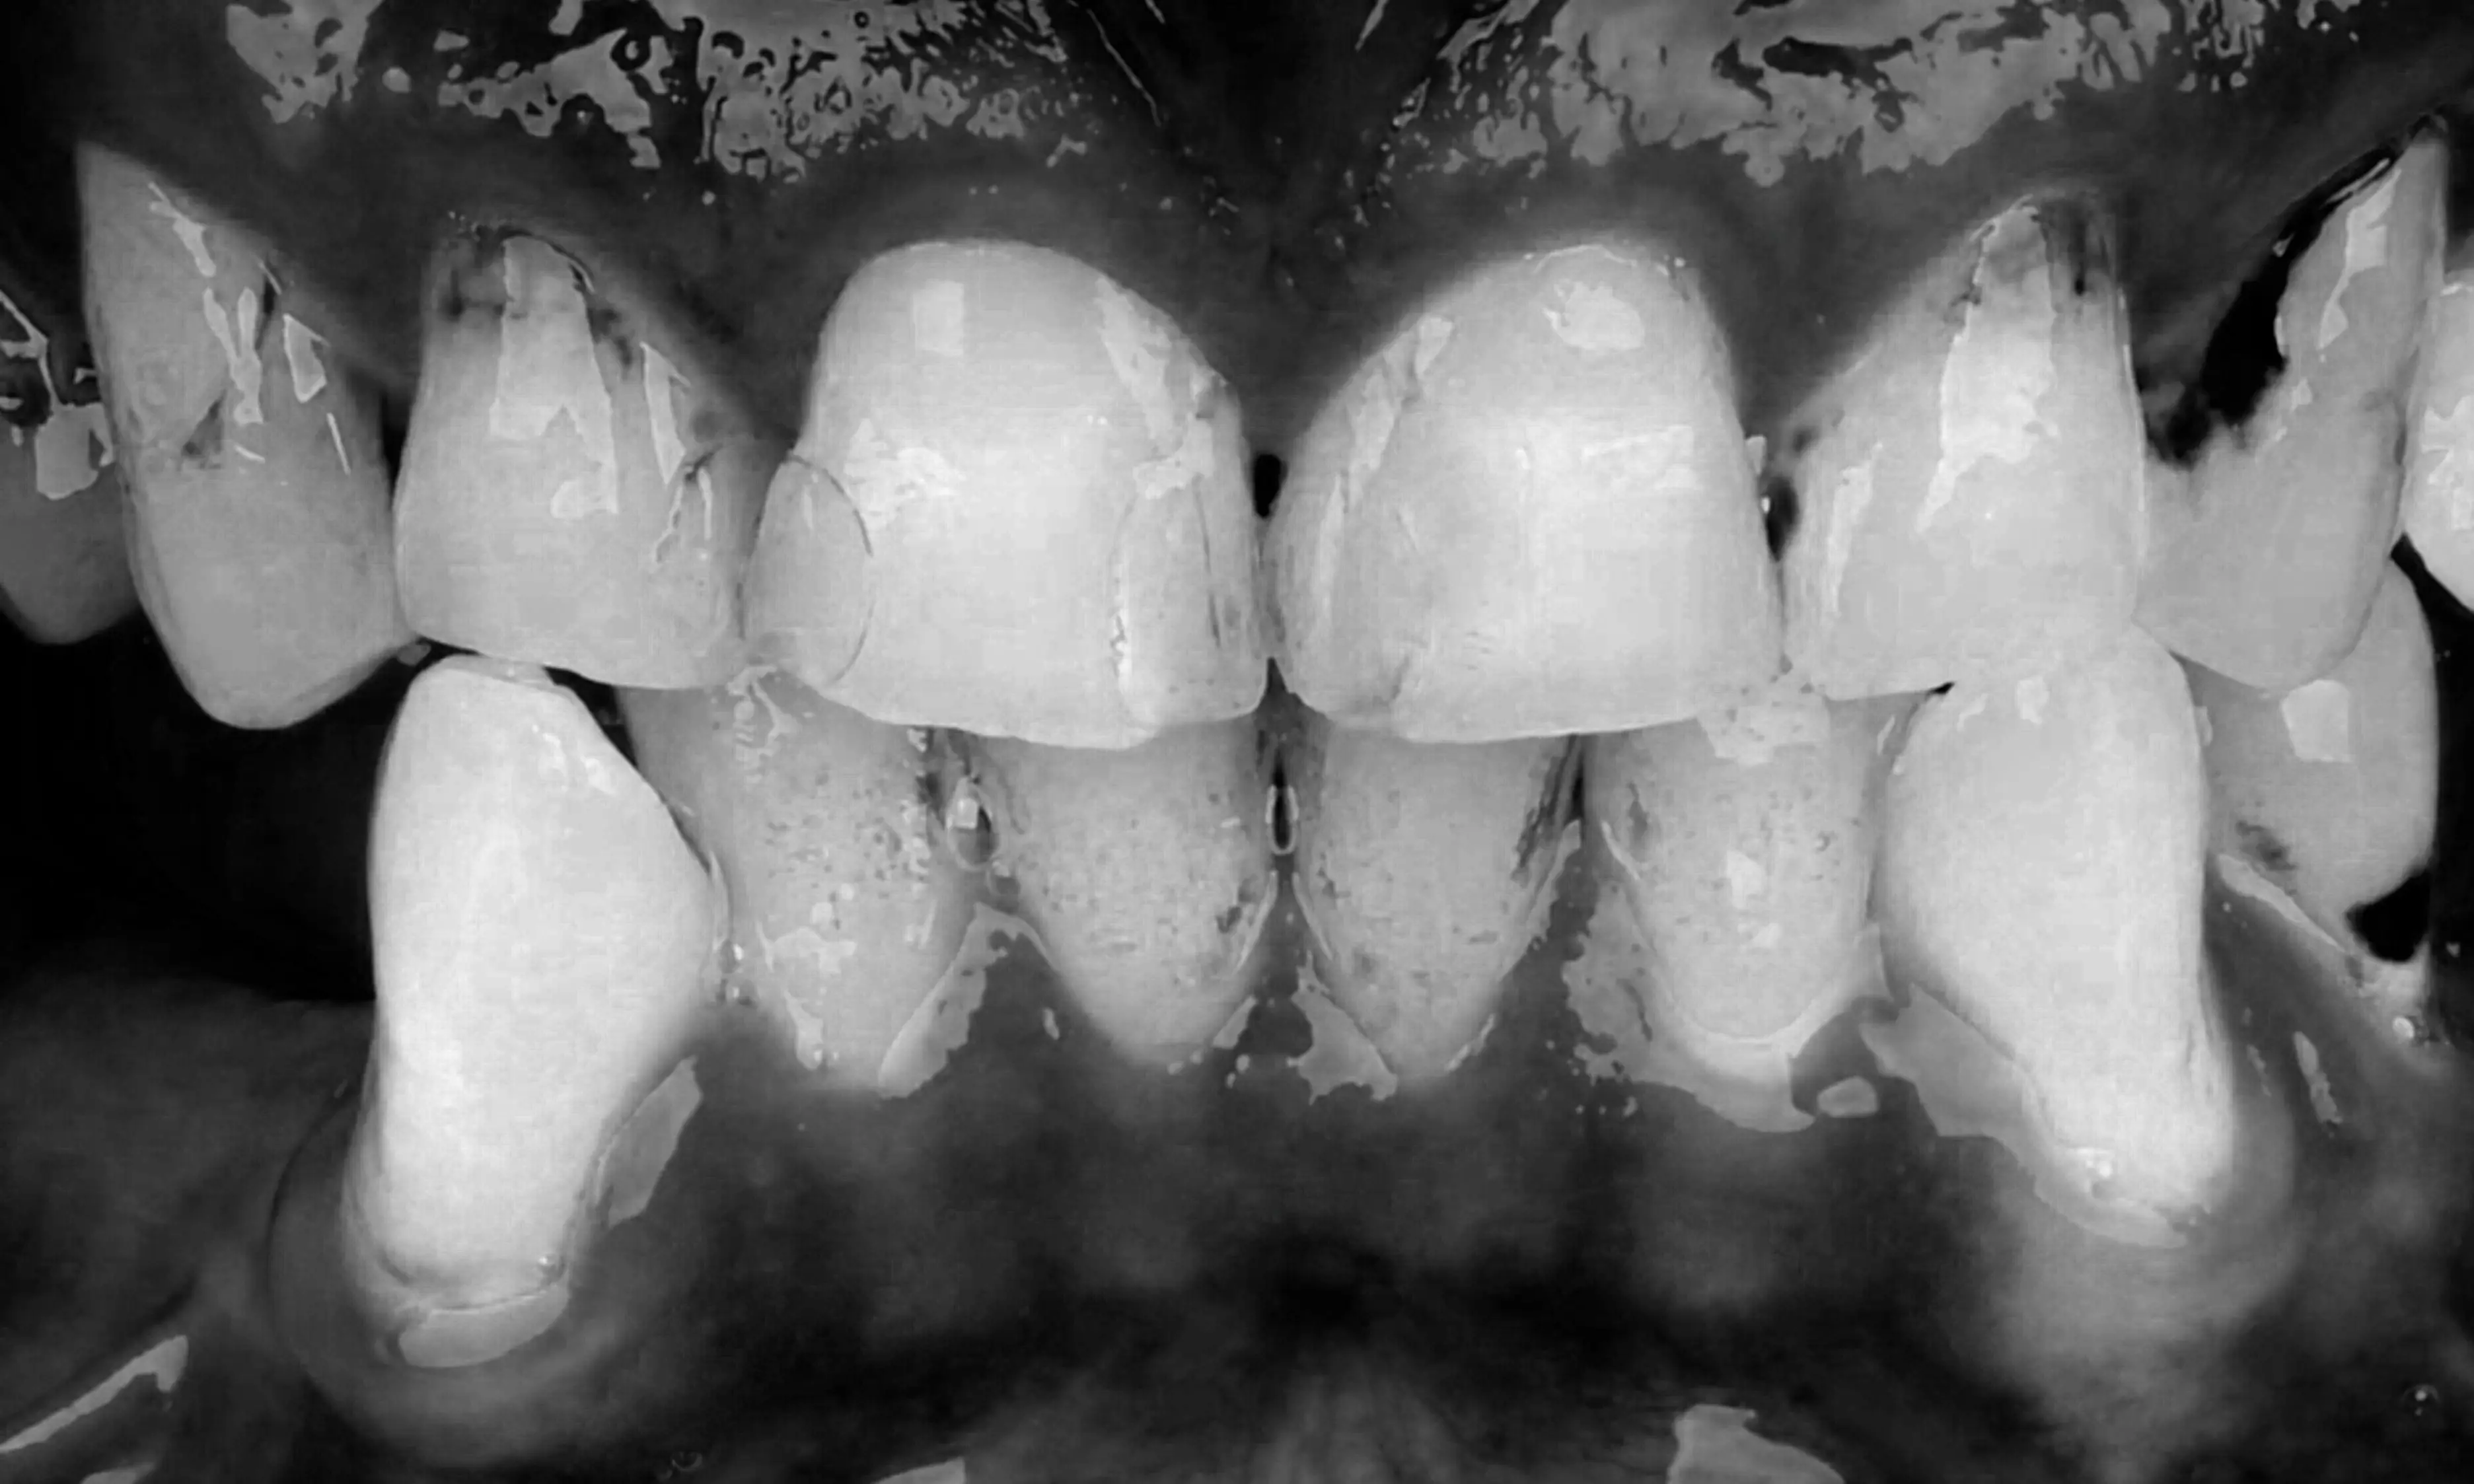

Mit moderner Technologie und optimiertem Workflow: Zahntechnik ohne Kompromisse.

Das Beste aus zwei Welten: Handwerkliche Perfektion beim Schichtkonzept und digitale Höchstleistung durch unser Planungskonzept. Das Ergebnis ist ein hochoptimierter Prozess, der von der ersten Planung bis zur finalen Eingliederung keine Kompromisse zulässt – effektiv und präzise.

Für uns bei dental shapes war dieses Projekt die Gelegenheit, die Grenzen einer modernen Zahntechnik neu zu definieren.